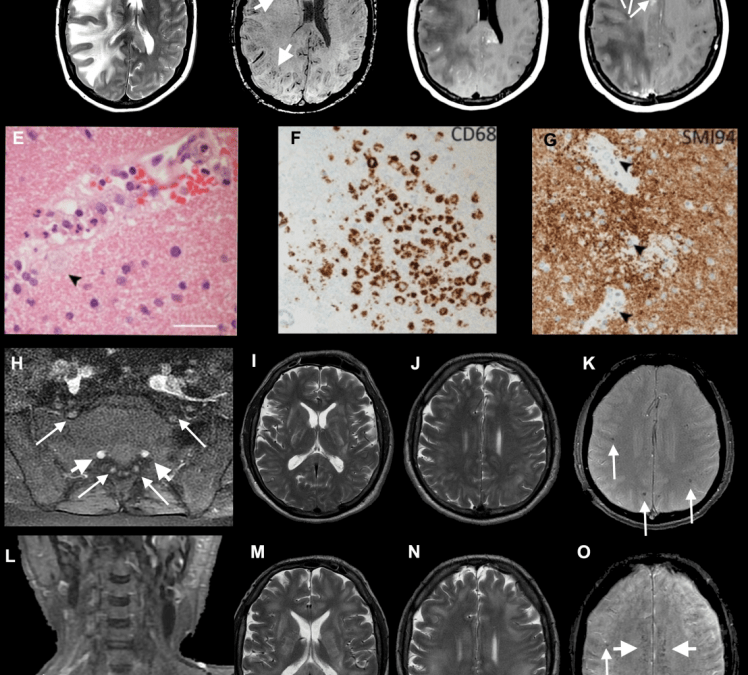

Brain images of a patient with acute demyelinating encephalomyelitis.Paterson et al.

Some patients suffered brain inflammation as a result of a rare disease called acute disseminated encephalomyelitis, which can cause numbness, seizures, and confusion. One patient in the study even hallucinated monkeys and lions in her home.